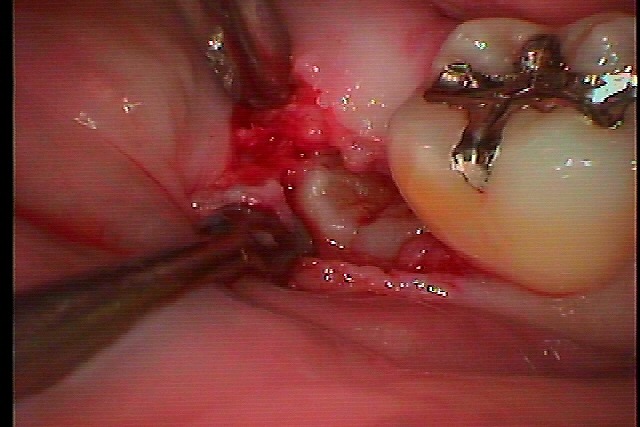

右下水平埋伏歯の難抜歯 全く見えていないところに歯が存在していますが、、、、|お知らせ |広島市安佐南区の歯科医院 右下水平埋伏歯の難抜歯 全く見えていないところに歯が存在していますが、、、、 トップ お知らせ・ブログ お知らせ 右下水平埋伏歯の難抜歯 全く見えていないところに歯が存在していますが、、、、 右下水平埋伏歯の難抜歯 全く見えていないところに歯が存在していますが、、、、 ここに親不知が埋まっています デンタルレントゲンにて 麻酔をかけて開けていきます このように見えてきます 抜歯を行いました 2針縫合して終了となります 1週後に抜糸していきます Web診療予約 初めての方へ 選ばれ続ける理由 院内設備について 歯が痛いしみる一般歯科 歯がぐらぐらする歯周病 健康な歯を保ちたい予防歯科 子供の虫歯予防をしたい小児歯科 銀歯をセラミックに審美歯科 白い歯を目指しませんか?ホワイトニング 矯正専門医がいるので安心矯正歯科 抜けた歯を補いたいインプラント・入れ歯 医院案内 スタッフ紹介 メリィハウス歯科クリニックオフィシャルホームページ ラベンダー歯科クリニックオフィシャルホームページ お知らせ・ブログ ホーム 診療科目 一般歯科 歯周病治療 予防治療 小児歯科 審美治療 ホワイトニング 矯正歯科 入れ歯・インプラント マウスピース矯正 初めての方へ 院長・スタッフ 設備紹介 医院案内・アクセス メニューを閉じる